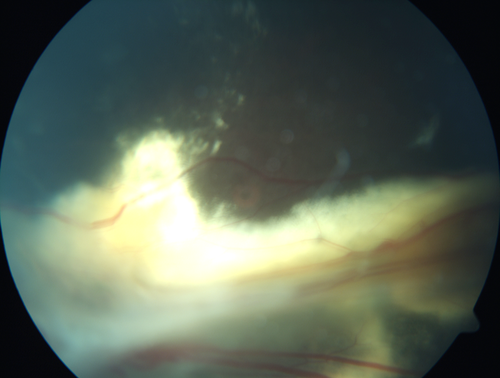

Familial Exudative Vitreoretinopathy - FEVR - Stage 4b OD

10 year old child with poor vision OD from birth.  The left eye had vascular remodelling in the temporal periphery with preretinal abnormalitlies seen on OCT.  The patient never returned for a fluorescein angiogram.  Left eye is either stage 1 or stage 2. no family history